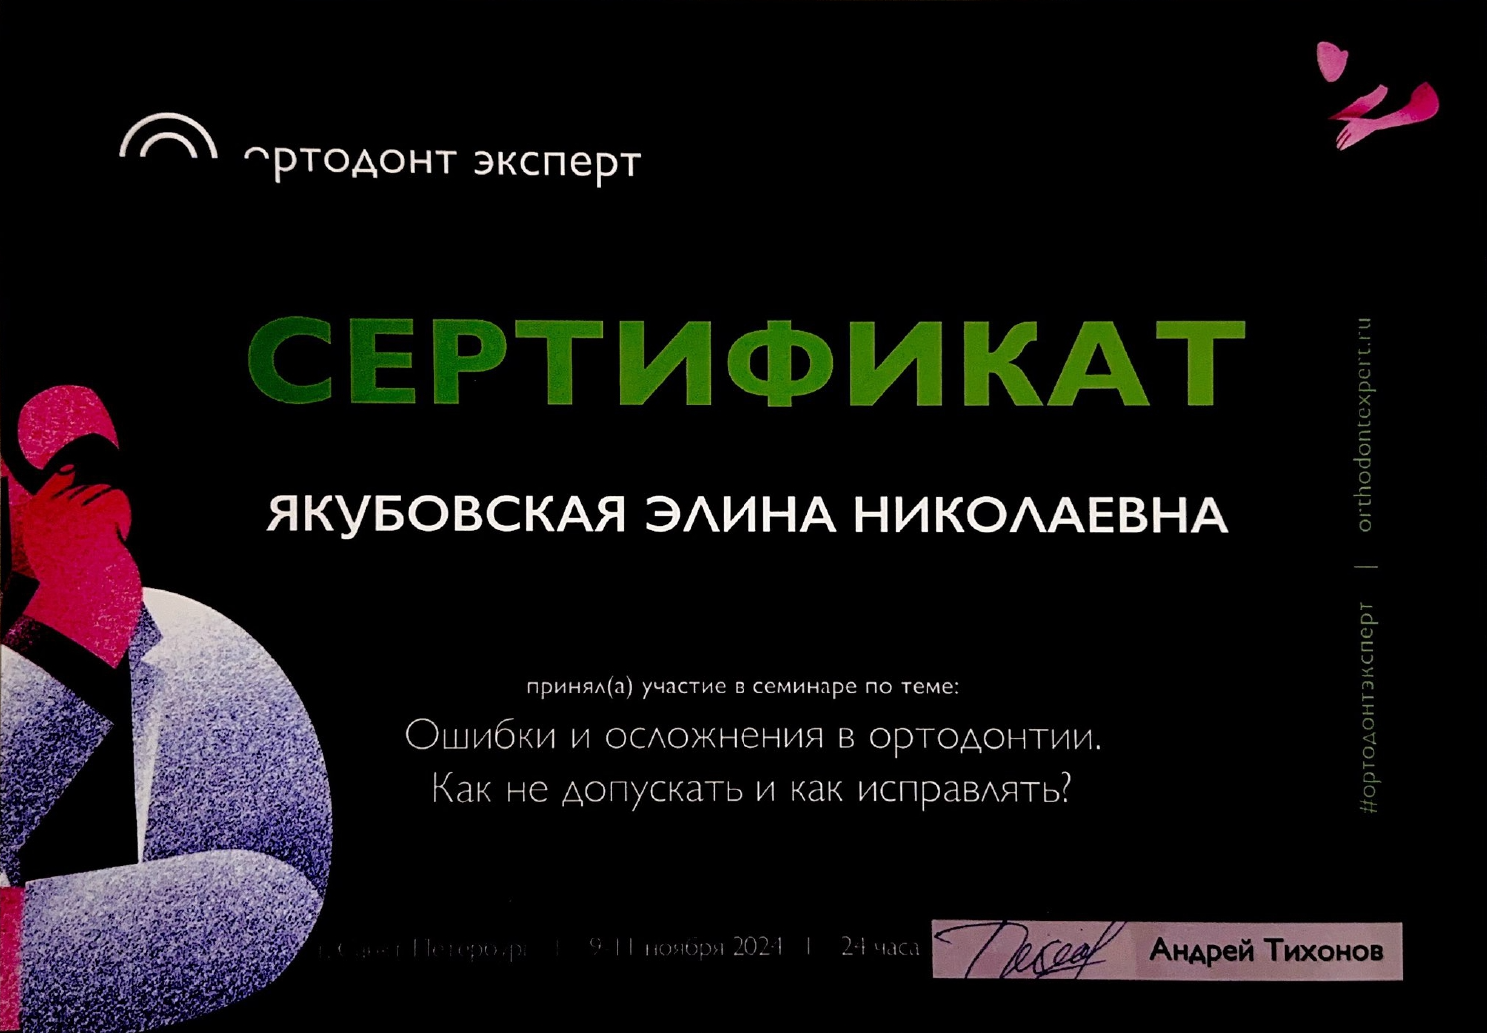

Специалисты клиник «Полный порядок» подбирают методику коррекции индивидуально, с учетом возраста, клинической ситуации и финансовых возможностей пациента. Так, в детском и подростковом возрасте для раннего лечения эффективны съемные аппараты - пластинки и трейнеры, а также тренажеры для губ и языка, занятия с логопедом, лечение частичной брекет-системой. Для взрослых пациентов мы рекомендуем самостоятельно лечение брекет-системами или капами элайнерами или в сочетании с хирургией. В некоторых случаях врач может комбинировать различные методики.

Профессиональное мнение